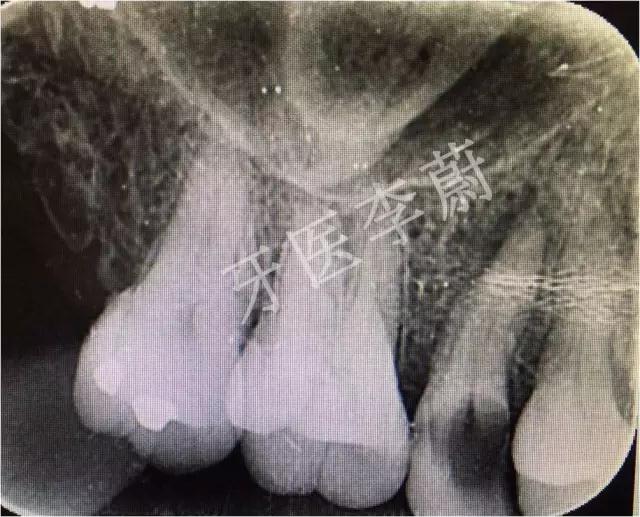

X片示:15残冠影,根尖有骨密度降低影。

局部X牙片

15牙根管预备试尖片